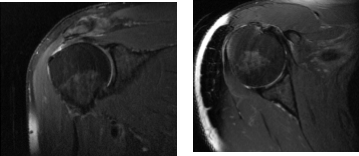

The patient presented MRI results that have shown small full-thickness tear of the distal supraspinatus tendon at its insertion measures 1.3 x 1.5 cm. Background tendinosis and attrition of the torn supraspinatus tendon. Tendinosis of the superior distal subscapularis tendon.

No rotator cuff muscle atrophy. Mild tendinosis, intra-articular long head of the biceps tendon with mild tenosynovitis. Tear of the posterosuperior labrum. Small subacromial subdeltoid bursitis communicates freely with small joint effusion. Mild osteoarthritis of the AC joint.

MRI Right Shoulder Non-contrast